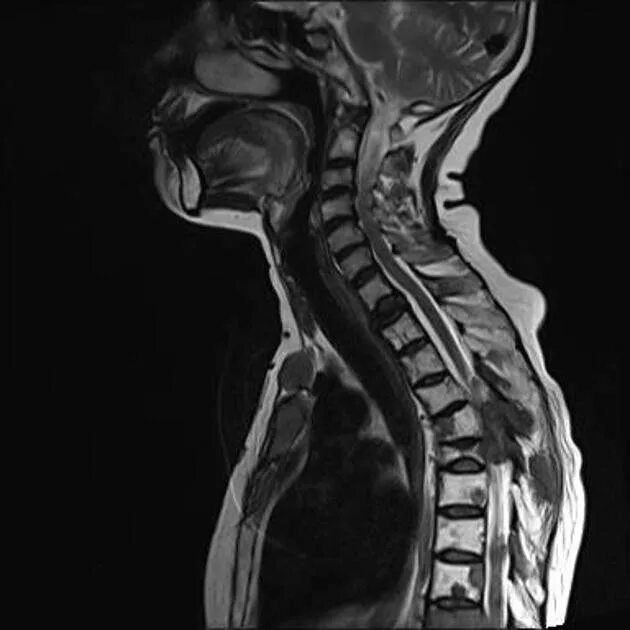

Метастазы костей мрт